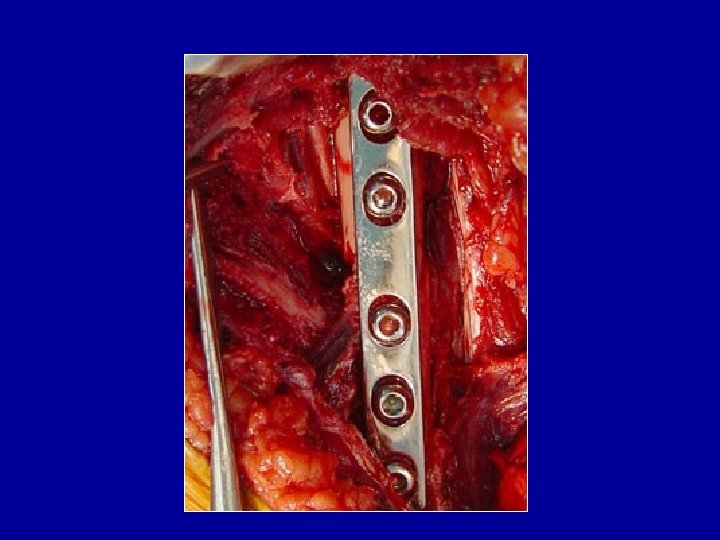

Ostéosynthèse du tibia par plaque vissée Plaque sur la corticale externe ou interne

Photo J. Chouteau

Exemple d’ostéosynthèse mixte : clou verrouillé pour le tibia et plaque pour le péroné